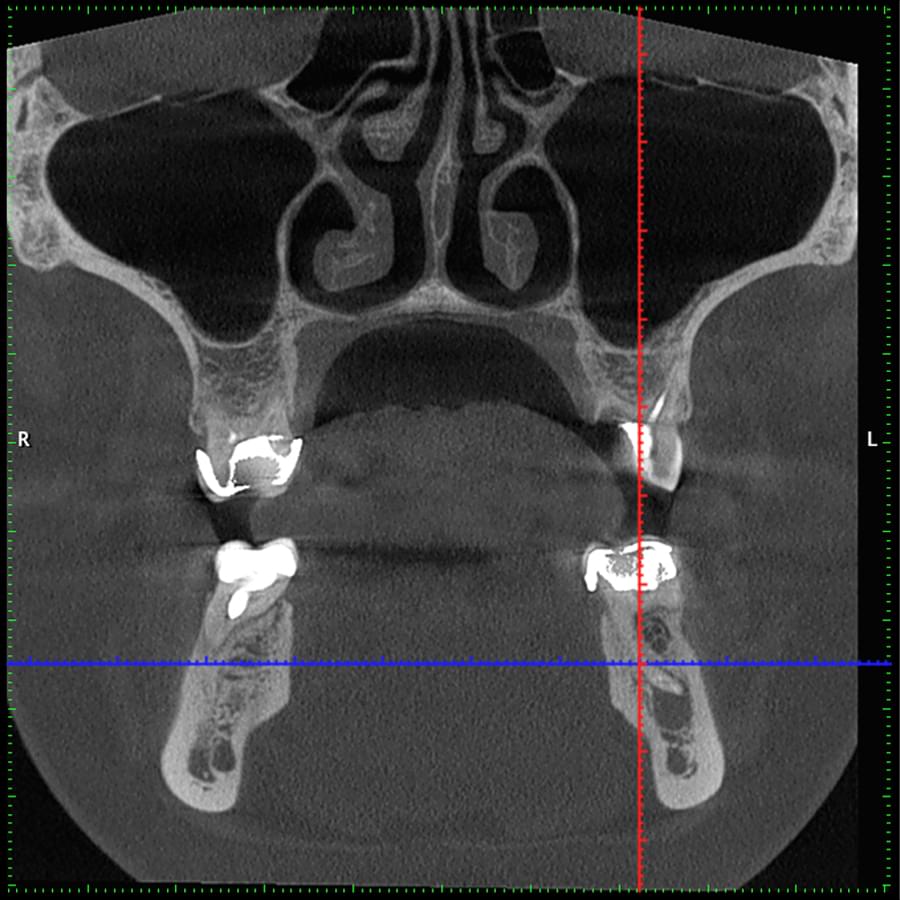

3D цефалометричний аналіз є сучасною технологією, яка дозволяє отримувати точніші,

комплексніші та надійніші дані про зубну та скелетну структуру. Ця технологія може стати

великим кроком в перед для ортодонтів, які хочуть забезпечити найкраще можливе лікування

своїх пацієнтів.

Основні переваги 3D цефалометричного аналізу:

Точність: 3D цефалометричний аналіз забезпечує точніше визначення розмірів та відстаней між

зубами та кістковими структурами.

Комплексність: ця технологія дозволяє отримувати детальні дані про різні структури, такі як

кістка та м'язи, що дозволяє ортодонтам докладніше досліджувати деякі патології та планувати

лікування.